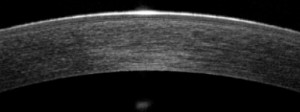

Es mas, la tecnología de la que disponemos ,TOPOGRAFOS de ultima generación ,que nos dan información del astigmatismo de cara anterior y posterior de nuestra cornea y OCT anterior (tomografía de coherencia óptica), que permite, mediante un haz de láser infrarrojo, obtener una imagen microscópica y en tres dimensiones de la córnea. Gracias “podemos ver cómo la lente de contacto se apoya en cada punto de la córnea de forma objetiva y, por tanto, diseñarla absolutamente a medida”, nos facilita en todo momento las adaptaciones complicadas y no tan complicadas.